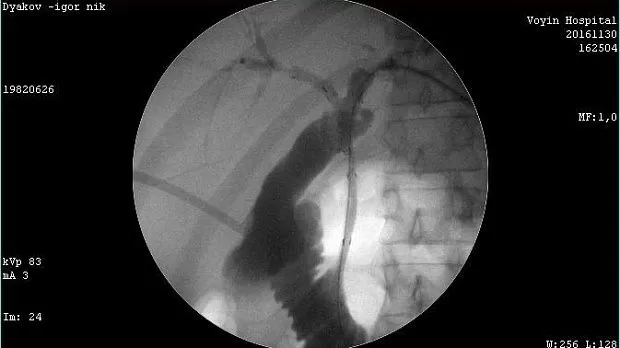

Молодой человек 33 г. Диагноз подтвержден. Стентирован пластиковыми стентами, потом самораскрывающимися. Одномоментно анте и ретроградно - с хорошим результатом. Дальше был поставлен в очередь на трансплантацию. Дальнейшая судьба не известна.